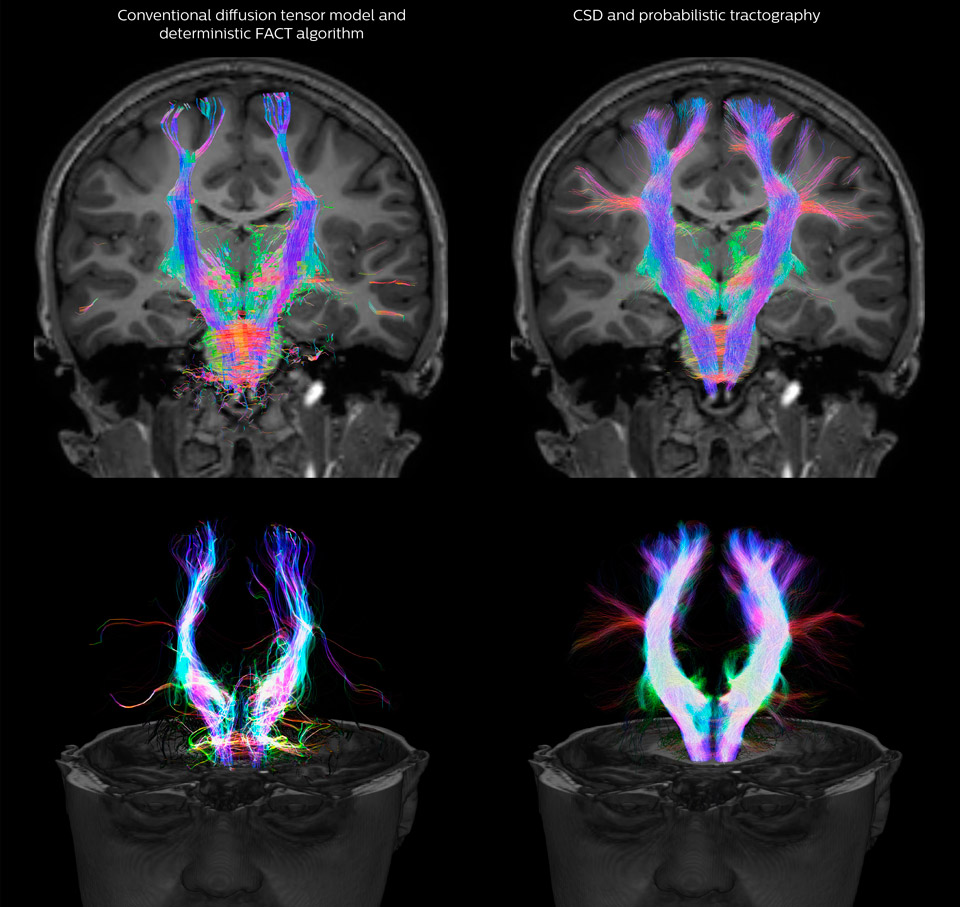

Comparison of fiber tractography methods

Fiber tractography of the corticospinal tract with seed region of the posterior limb of the internal capsule. Different processing based on the same data.

UVM research comparison of fiber tractography methods

All images were created from the same acquisition in a child using Ingenia 3.0T CX and 32-channel dS Head coil. Diffusion data was acquired at b-values 0, 500, 1000, 2000, 3000. The use of high b-values (3000 s/mm2) effectively suppresses extra-axonal water signal and provides high angular resolution.

Fiber tracking based on CSD analysis of multishell DWI data and probabilistic tractography.

Fiber tracking from the left and right hippocampi to the fornix.

Fiber tracking from the left and right hippocampi to the fornix (green), and the corticospinal track based on a seed region of the posterior limb of the internal capsule.